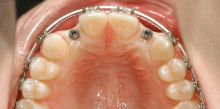

Kieferorthopädische Miniimplantate sind temporäre Implantate, die zur skelettalen Verankerung in den Kieferknochen eingesetzt und nach ihrem Einsatz...

Kieferorthopädische Miniimplantate sind temporäre Implantate, die zur skelettalen Verankerung...